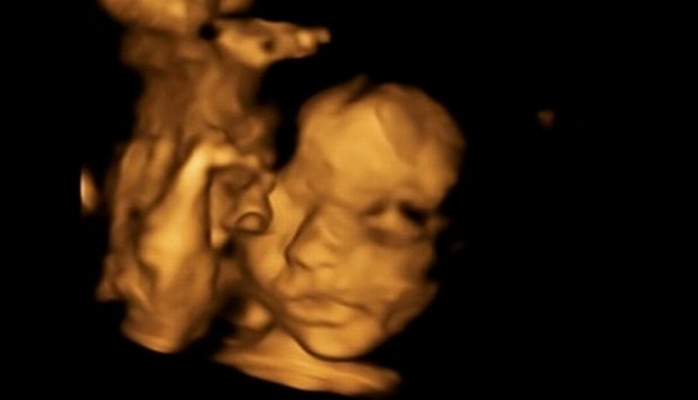

В МИРЕ Ребенка вынули из утробы матери ради операции и вернули на место Автор: Leyla Tagiyeva 12 February 2019, 11.35